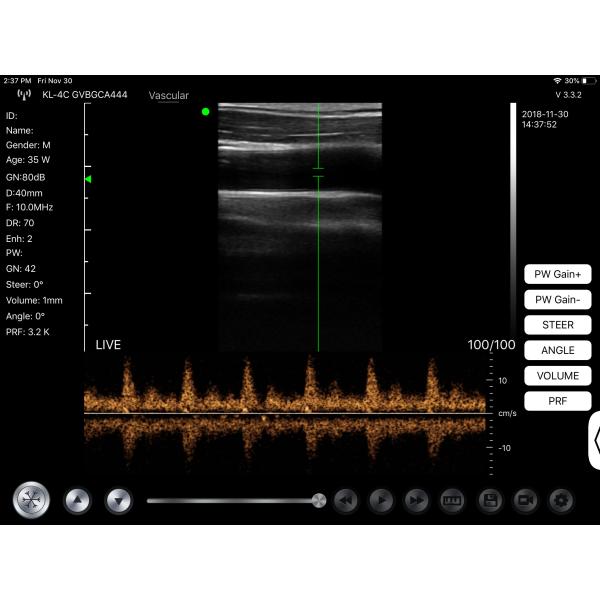

Ultrasound USB Probe Wireless Transducer For Ultrasound GH G10UR G10UL

G10UR G10UL is a wireless & USB ultrasound probe scanner.This USB/wireless probe scanner with integrated ultrasound circuit boards inside, can wireless connect to the IOS/Android/Windows device that after installed ultrasound software, then realize the functions of a ultrasound scanner.It is small and smart, convenient for carry and operation.

| Display mode | B, B/M, color, PW, PDI |

G10UR G10UL Medical Hospital Equipments Ultrasound USB Probe Wireless Transducer Images |